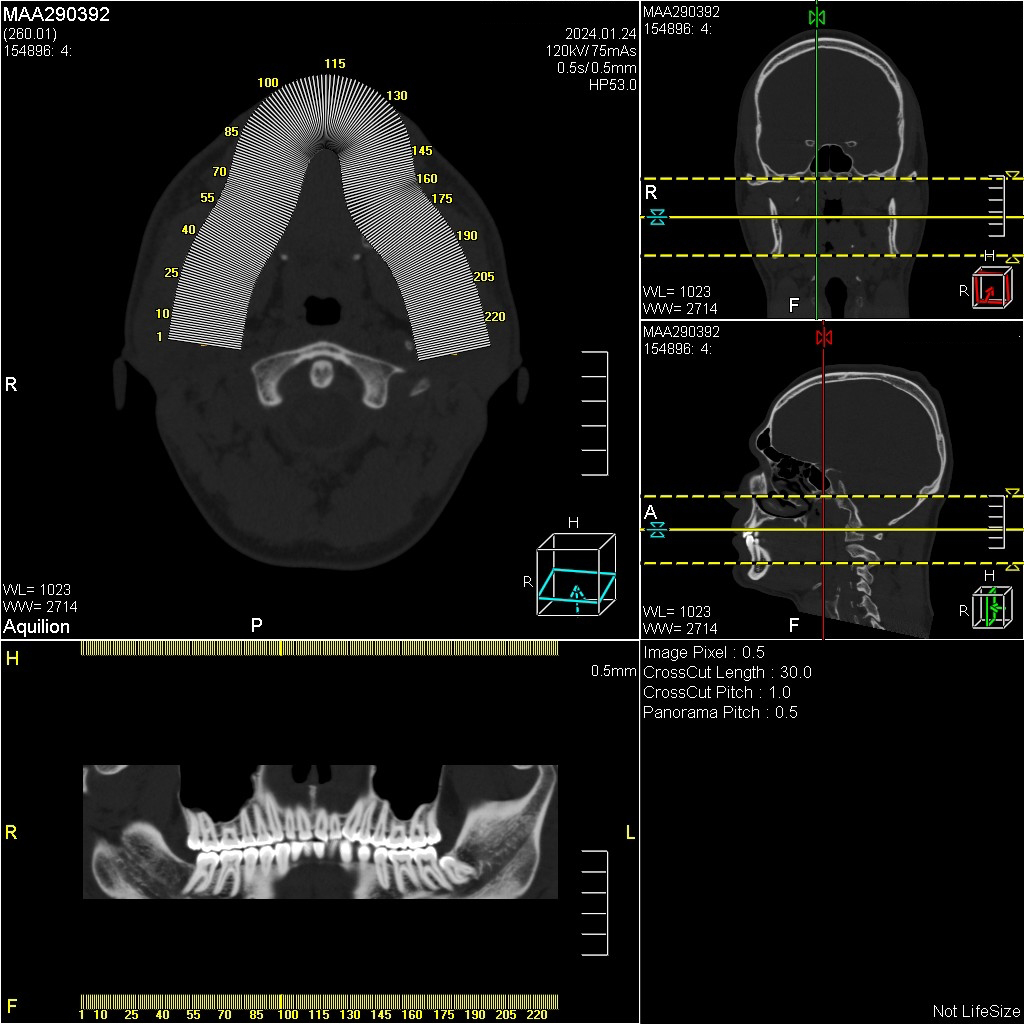

Мультиспиральная дентальная компьютерная томография (МДКТ или, как ее еще называют, КТ зубов) – это современный высокоточный метод лучевой диагностики, с помощью которого получают объемные цифровые изображения всей зубочелюстной системы. В основе метода лежит применение рентгеновского излучения и последующая цифровая обработка полученных данных специальными компьютерными программами.

Мультиспиральный томограф выполняет послойное сканирование области верхней и нижней челюстей с помощью рентгеновских лучей, а затем, используя компьютерную обработку данных, создает 3D-модели исследуемой зоны. Современные модели томографов проводят круговое сканирование по спирали, делая срезовые снимки на расстоянии 0,5 мм друг от друга. Затем на основе этих данных реконструируются детальные изображения челюстно-лицевой области в трехмерном формате.

Исследование занимает всего пару минут. Данные, полученные при сканировании, проходят цифровую обработку и выводятся на монитор компьютера в виде 3D-изображений. Врач-рентгенолог внимательно анализирует данные и выдает заключение.

Высокая информативность исследования за счет детальных снимков и наглядных пространственных 3D-реконструкций позволяет увидеть то, что недоступно для визуального осмотра и обычного рентгеновского обследования.

Дентальная КТ показывает: